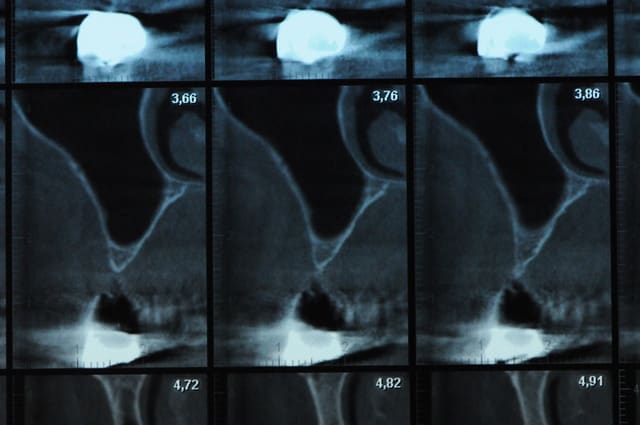

scanner...

Dsc 4910 aitqw8 - Eugenol

Dsc 4916 qjrote - Eugenol